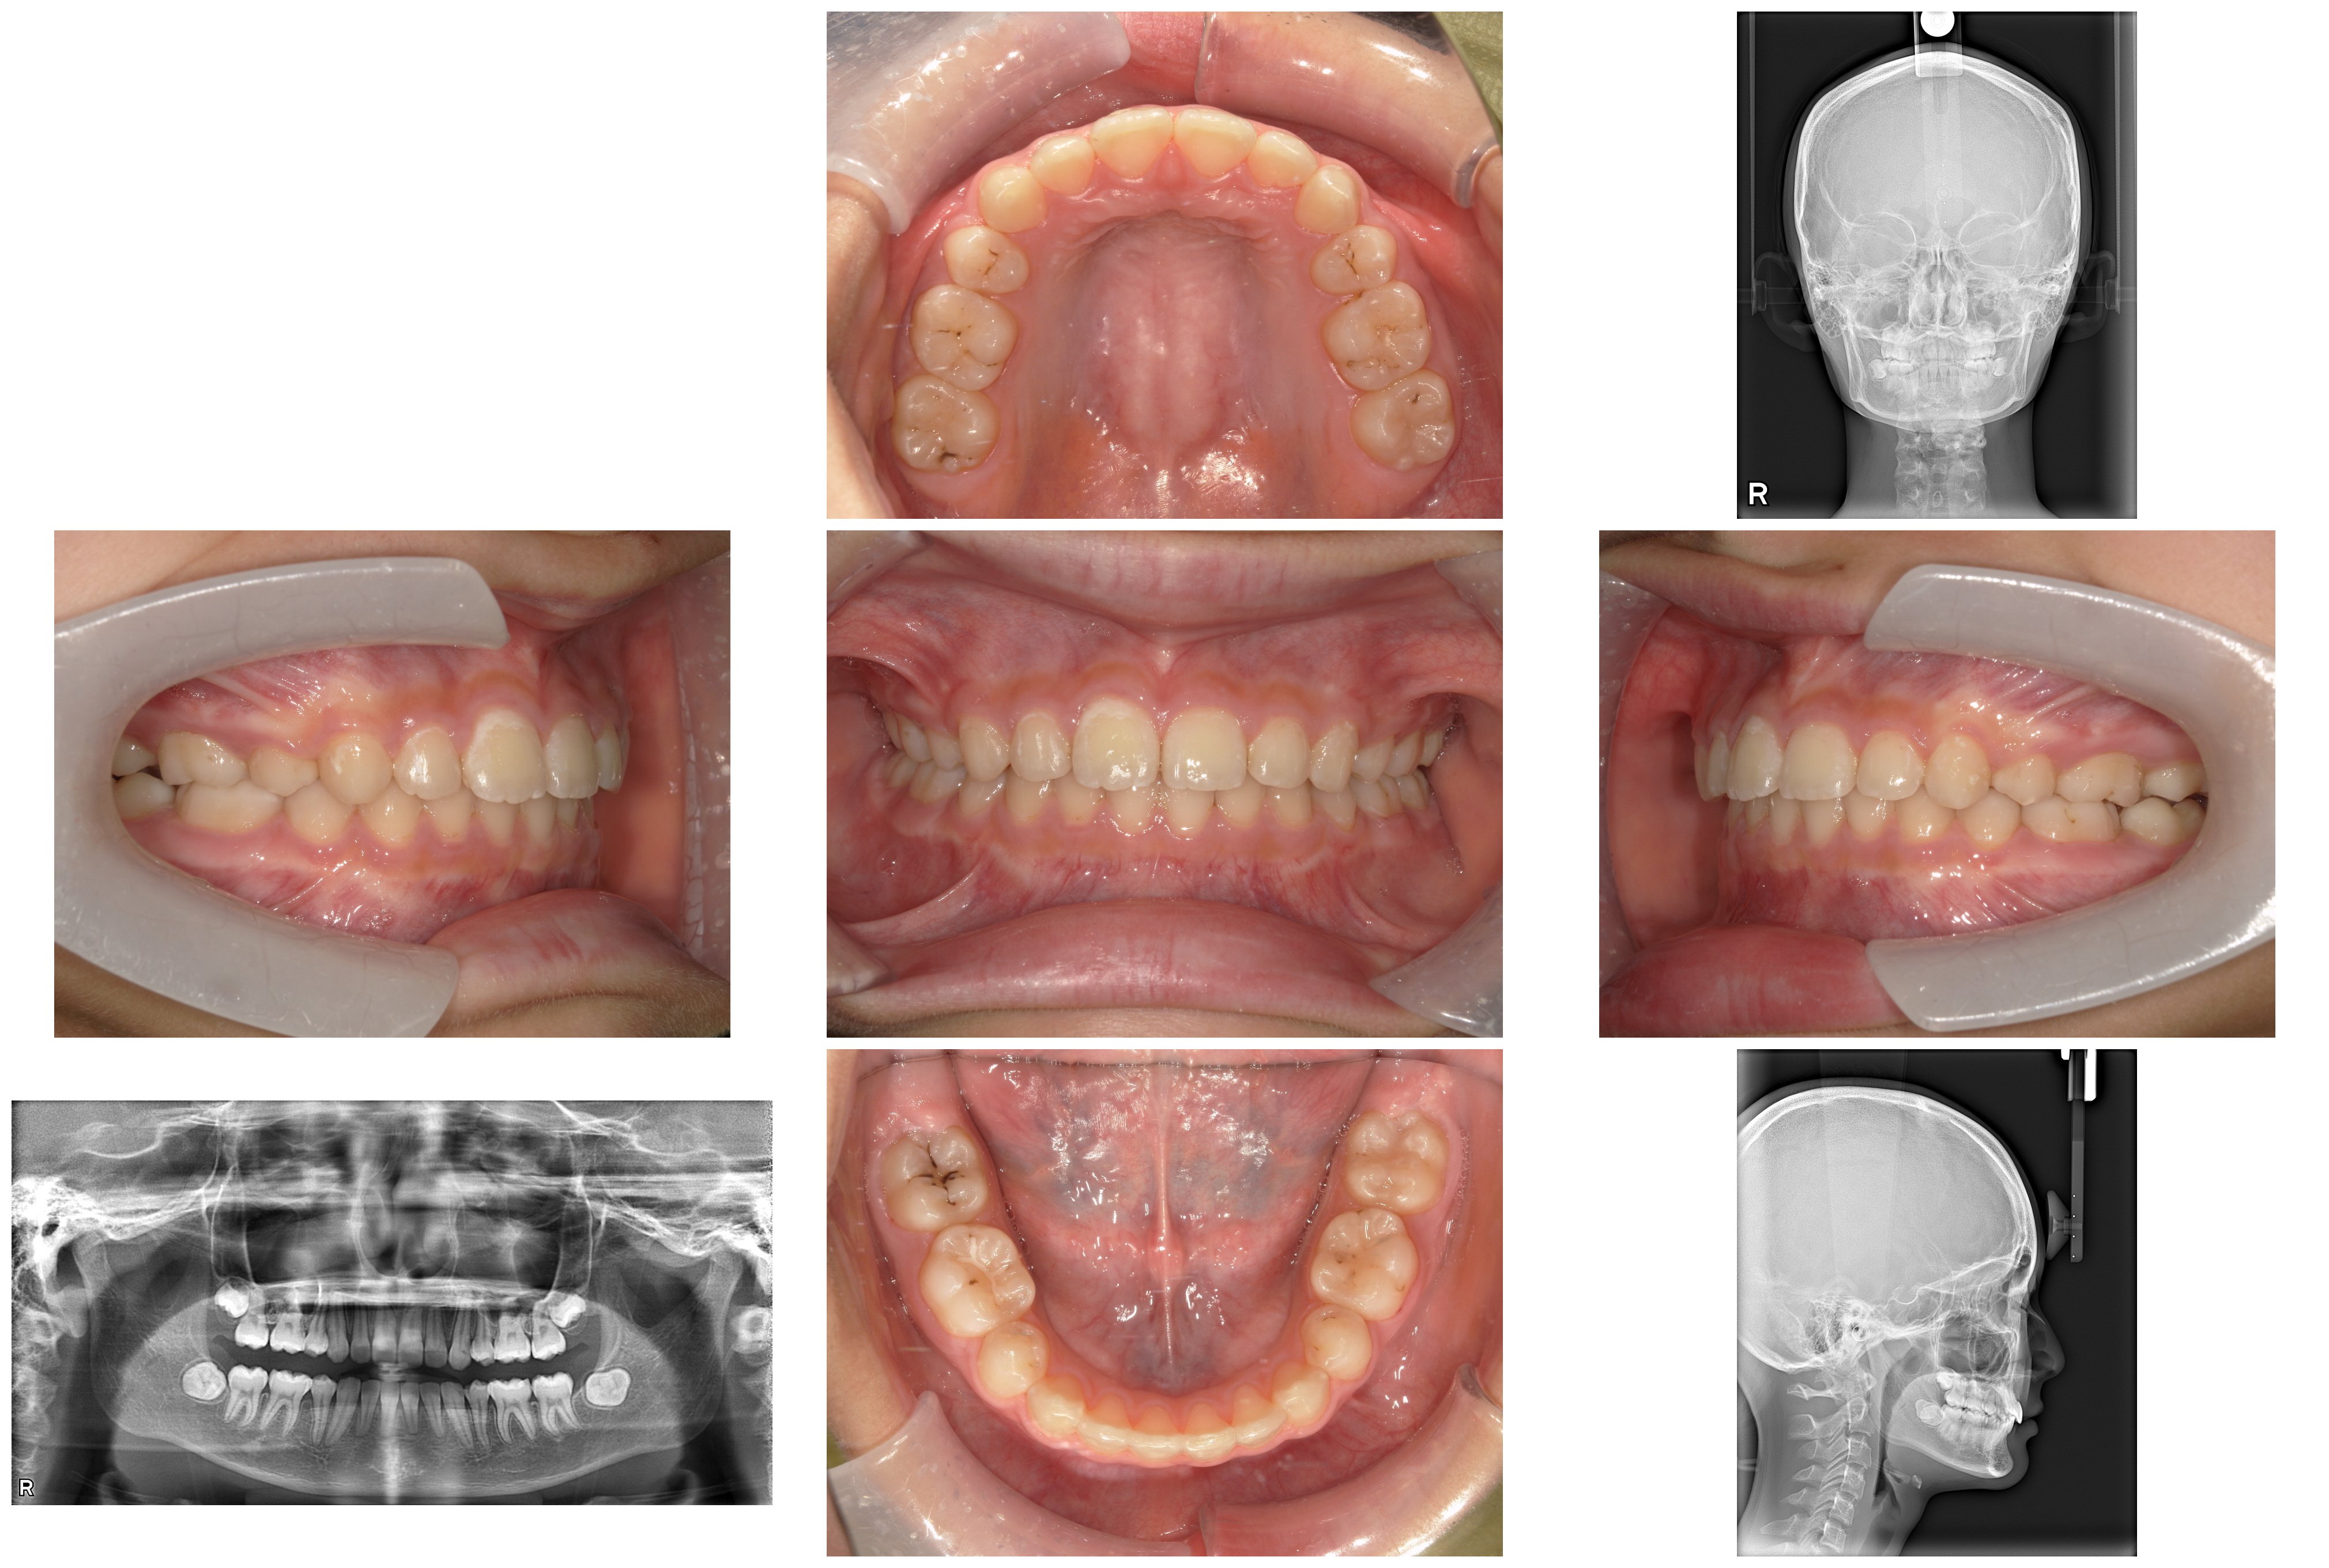

今回は、14歳の患者さんの「出っ歯(上顎前突)」と「奥歯の萌出不全」を伴う、一見簡単そうに見えるけれども難易度の高めな矯正治療のプロセスを詳しく解説します。

精密検査の結果、単なる「前歯の傾き」だけではない、骨格や奥歯の生え方に由来する複雑な要因が明らかになりました。

軟組織:横顔を確認すると、口元が前に出て見える「凸型の横顔」でした。

骨格:上あごに比べて下あごが後ろに位置している骨格で、いわゆる出っ歯になりやすい骨格のタイプでした。また、咬む力が強く、顔の縦の長さがやや短い傾向がある骨格の特徴もみられました。

歯系: 前歯の前後的な差が著しく大きい「著大なオーバージェット」と、下の前歯が上の前歯に深く隠れてしまう「過蓋咬合(かがいこうごう)」が認められました。

大きな問題点: 本来なら生えきっているはずの下顎左右の第二大臼歯(一番奥の7番目の歯)が、萌出時期を過ぎても歯ぐきに埋まったままの「半萌出状態」となっていました。